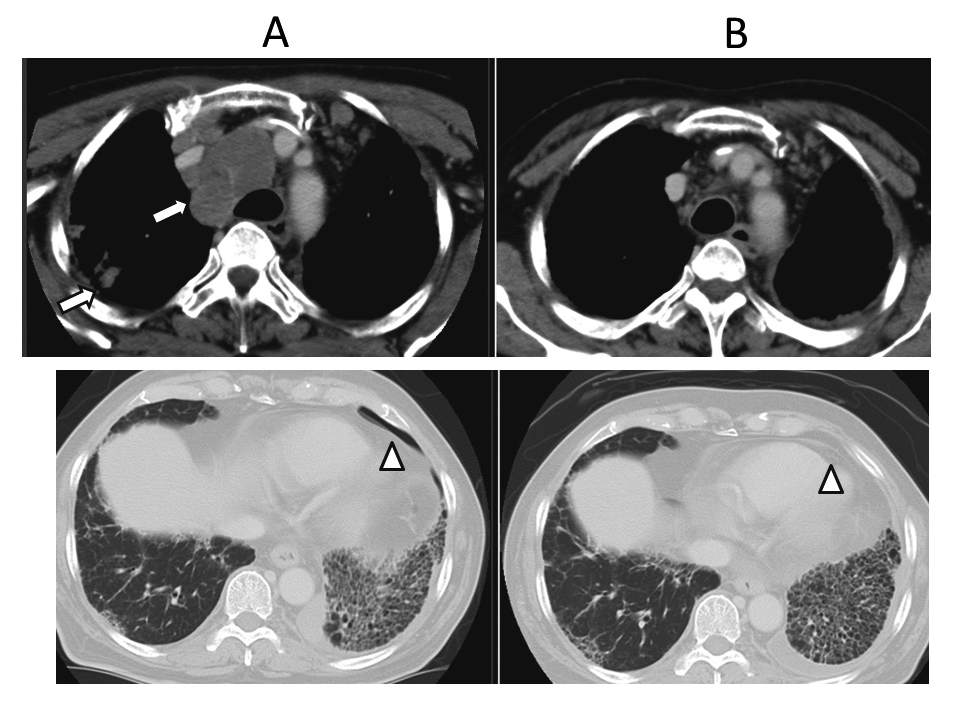

A PET-CT scan performed 1 month after the discontinuation of the DOC therapy revealed increased metastases to the mediastinal lymph node and lung (Figure 4A). The patient received a second opinion at another hospital where pazopanib and anthracycline-based chemotherapy were suggested. However, because the patient was concerned about the potential aggravation of IP, he refused these therapies in August 2014 and requested for best supportive care (BSC).

Another CT scan performed in October 2014, 2 months after BSC was initiated, revealed further increased metastases to the mediastinal lymph node and lung and aggravation of IP and pneumothorax (Figure 5A). However, to our surprise, a CT scan performed in April 2015, 8 months after BSC was initiated, revealed decreased metastases to the mediastinal lymph node and lung, and the pneumothorax had spontaneously disappeared (Figure 5B). In the next follow-up PET-CT scan performed in October 2015, 14 months after BSC was initiated, the primary lesion and other metastatic lesions were inconspicuous (Figure 4B). The patient had achieved spontaneous remission. Since the initial diagnosis, 40 months have passed. However, his IP has worsened and he currently requires sustained oxygenation. Informed consent was obtained from the patient for the publication of this case study.

A PET-CT scan performed in July 2014 revealed increased metastases to the mediastinal lymph node and lung (4A).

A PET-CT scan performed in October 2015, one year and two months after BSC, revealed almost no signs of the primary lesion and other metastatic lesions (4B).

A CT scan performed in October 2014 revealed increased metastases to the mediastinal lymph node and lung, and aggravation of the IP and pneumothorax (5A).

A lung CT scan performed in April 2015 revealed decreased metastases to the mediastinal lymph node and lung, and pneumothorax disappeared (5B).